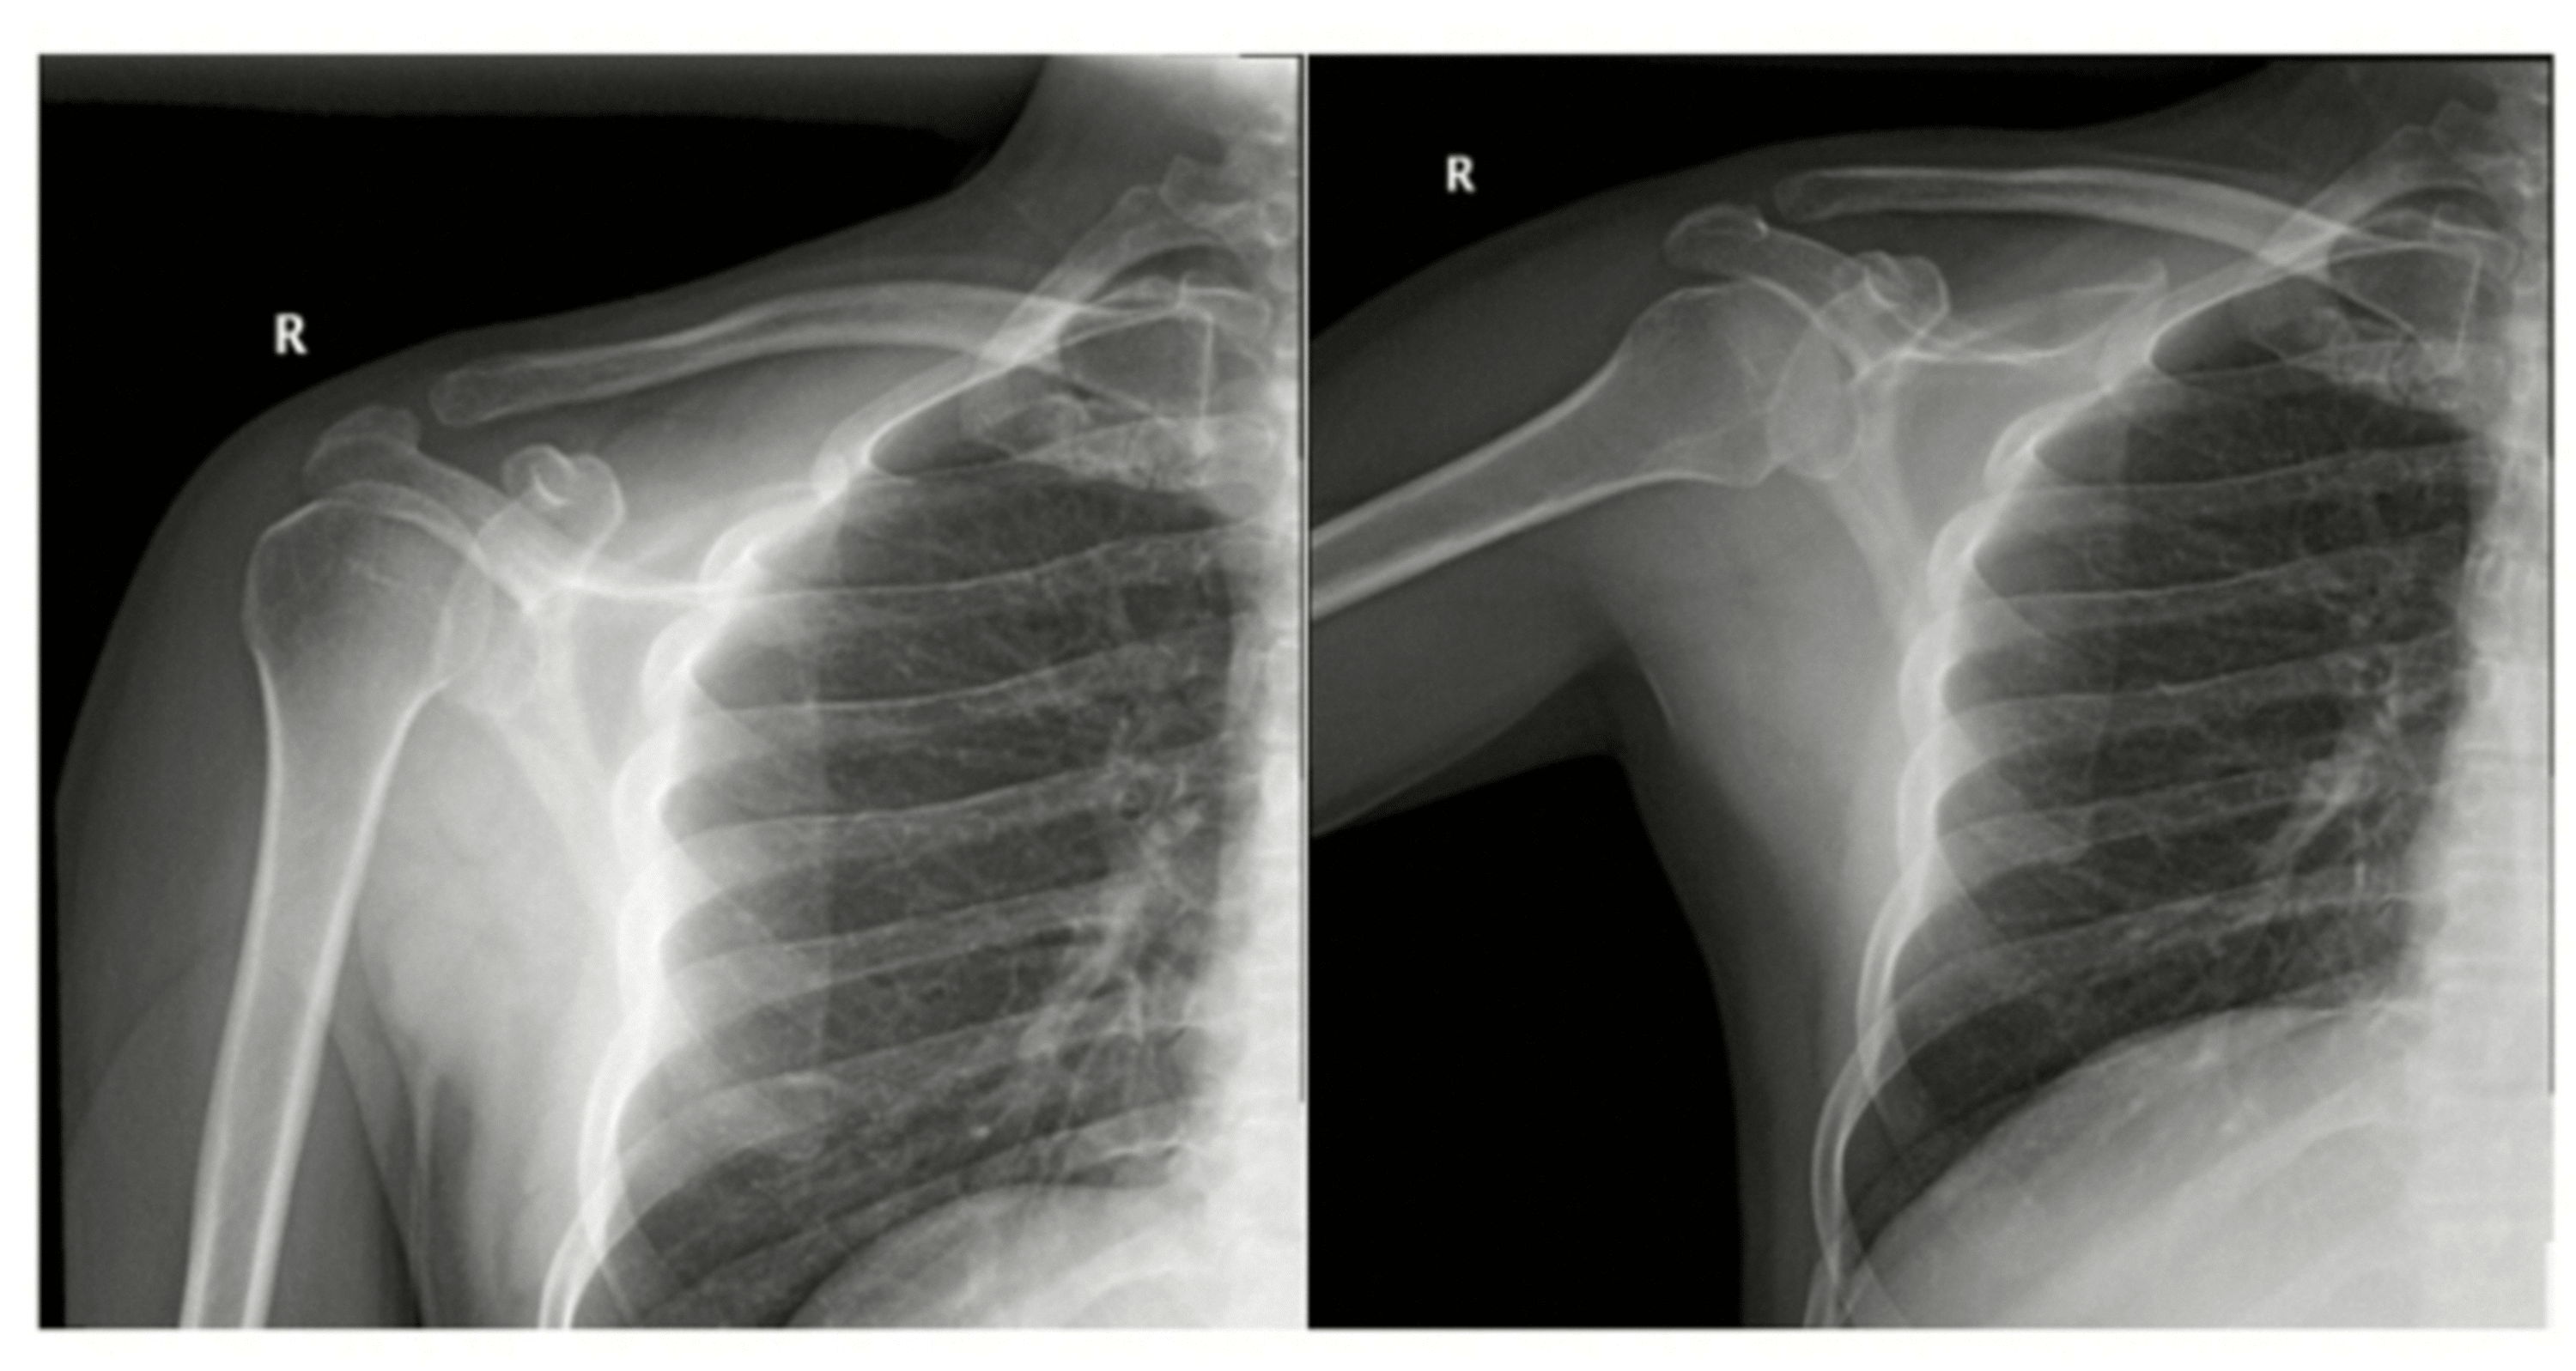

Figure 8 from Imaging pediatric sports injuries upper extremity Acute Sports Injuries Upper Extremity Dislocation Acute injuries and overuse injuries. Sports are a major cause of injury to the upper extremity in children and adolescents. Upper extremity sports injuries are exceedingly common and can have a large impact on athletic participation and performance. This article aims to educate emergency medicine physicians and pediatricians about the nature of acute traumatic sports. Acute injuries are caused by. Acute Sports Injuries Upper Extremity Dislocation.